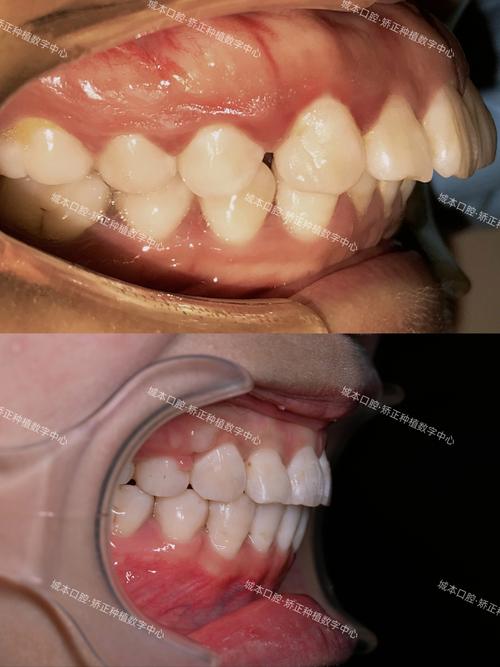

侧切牙内凹是口腔正畸中常见的牙齿畸形类型,主要表现为上颌侧切牙牙冠向舌侧倾斜,导致牙颈部唇侧膨隆、牙冠唇面看起来“凹陷”,常伴随牙齿扭转、牙间隙或咬合异常等问题,这种畸形不仅影响微笑美观,还可能因牙齿清洁困难增加龋病、牙周病风险,严重时会导致咬合功能紊乱,因此需通过正畸治疗进行干预。

从危害来看,美观上,内凹的侧切牙会破坏微笑弧线的对称性,尤其在前牙区显露明显时,影响个人形象;功能上,牙齿倾斜可能导致咬合时受力不均,长期易引发颞下颌关节紊乱;健康上,舌侧倾斜的牙齿邻接关系异常,易嵌塞食物,加之清洁难度增加,易导致牙龈炎、牙周炎,甚至牙槽骨吸收。